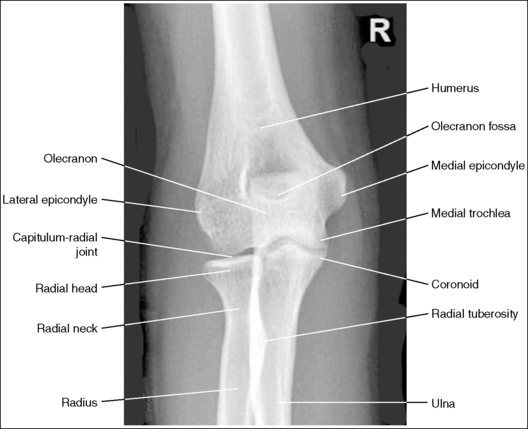

The proximal forearm is positioned in an AP projection. The radial head is superimposed over the lateral aspect of the proximal ulna by approximately 0.25 inch (0.6 cm). If included on the IR, the medial and lateral humeral epicondyles are demonstrated in profile at the extreme medial and lateral edges of the distal humerus.

The capitulum-radius joint is either partially or completely closed, and the radial head articulating surface is demonstrated. The olecranon process is situated within the olecranon fossa, and the coronoid process is visible on end.

• The anatomical relationships of the elbow on an AP forearm projection are slightly different from those on an AP elbow projection because of the difference in centering of the central ray. The central ray is placed directly over the elbow joint for an AP elbow projection but is centered distally to the elbow joint, at the midforearm, for an AP forearm projection. With distal centering, diverged rays record the elbow joint image instead of straight central rays, much the same as if the central ray were angled toward the elbow joint. Imaging the elbow with diverged rays projects the radial head into the capitulum-radius joint and causes the anterior margin of the radial head to project beyond the posterior margin, demonstrating its articulating surface.

The elbow is positioned in an AP projection. The medial and lateral humeral epicondyles are demonstrated in profile at the extreme medial and lateral edges of the distal humerus, and the radial head is superimposed over the lateral aspect of the proximal ulna by approximately 0.25 inch (0.6 cm). The coronoid process is demonstrated on end.

• Detecting elbow rotation. Rotation of the elbow is a result of poor humeral epicondyle positioning and can be identified on an image when (1) the epicondyles are not visualized in profile, (2) the radial head is demonstrated with more or less than 0.25 inch (0.6 cm) superimposition of the ulna, and (3) the coronoid process is seen in profile. The smaller, lateral humeral epicondyle is more sensitive to rotation, moving out of profile with only a slight degree of elbow rotation. If the epicondyles are not demonstrated in profile, evaluate the degree of radial head superimposition of the ulna to determine how to reposition for an AP projection. If more than 0.25 inch (0.6 cm) of radial head is superimposed over the ulna, the elbow has been internally rotated (see Image 74). If less than 0.25 inch (0.6 cm) of the radial head is superimposed over the ulna, the elbow has been externally rotated (see Images 75 and 76).

The radial tuberosity is demonstrated in profile medially, and the radius and ulna are parallel.

The capitulum-radius joint is open, the radial head articulating surface is not demonstrated, the olecranon process is situated within the olecranon fossa, and the coronoid process is demonstrated on end.